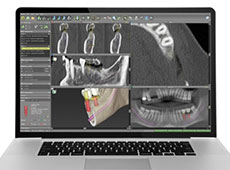

血管や神経の位置、骨量を正確に把握するため、当院では3Dによるインプラントシミュレーションを行います。通常のレントゲンでは撮影出来なかった箇所を把握出来る事により、より安全な埋入手術が可能になります。

サージカルステント・3Dシミュレーションはインプラント価格に含まれています!

ご来院時にCT撮影を行います。撮影した画像をもとに、3Dシミュレーションを行い、患者様に分かり易くインプラント治療をご説明いたします。

初回無料相談時に撮影したCT画像をもとに患者様ごとにそれぞれの治療計画を立案します。治療期間や治療費用の確定もこの時点でご提示します。